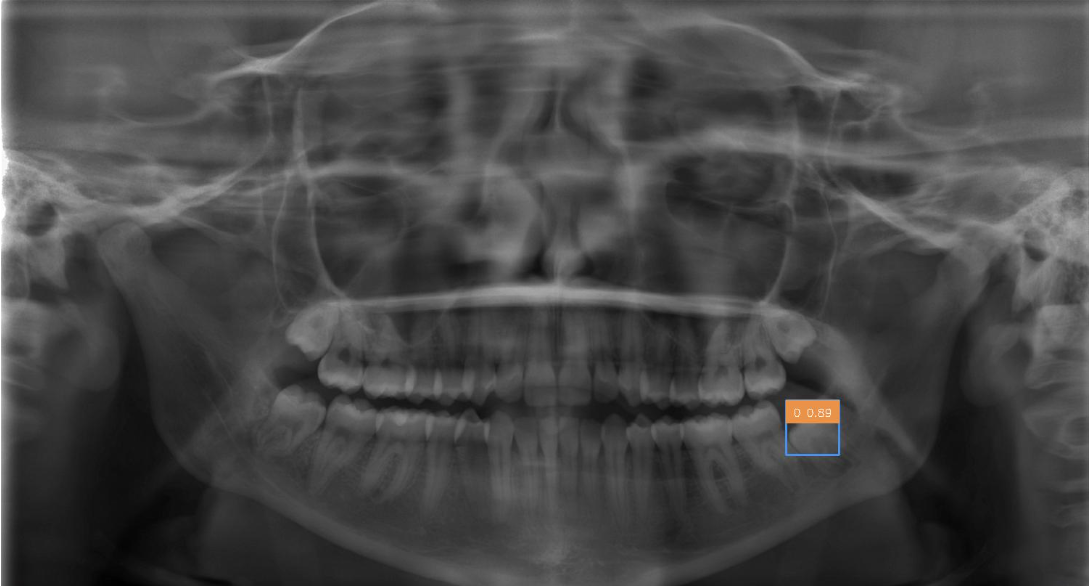

Como mostrado na imagem do dataset acima, temos três pastas chamadas: CREATML (JSON), PascalVOC (XML), YOLO (TXT) com as coordenadas dos cistos, que se mostrarmos utilizando as bibliotecas OpenCV e Matplotlib temos imagens como as ao lado.